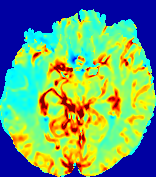

LesionRefer to captionRefer to captionRefer to captionRefer to captionRefer to captionRefer to caption𝐕rgbsubscript𝐕𝑟𝑔𝑏{\bf{V}}_{rgb}Refer to captionRefer to captionRefer to captionRefer to captionRefer to captionRefer to caption𝐕2subscriptnorm𝐕2{\|\bf{V}}\|_{2}Refer to captionRefer to captionRefer to captionRefer to captionRefer to captionRefer to captionRefer to caption3.53.53.52.82.82.82.12.12.11.41.41.40.70.70.70.00.00.0(mm/s)𝑚𝑚𝑠(mm/s)D𝐷DRefer to captionRefer to captionRefer to captionRefer to captionRefer to captionRefer to captionRefer to caption0.0200.0200.0200.0160.0160.0160.0120.0120.0120.0080.0080.0080.0040.0040.0040.0000.0000.000(mm2/s)𝑚superscript𝑚2𝑠(mm^{2}/s)Slice #1Slice #2Slice #3Slice #4Slice #5Slice #6

Figure 4: PIANO feature maps for another patient in the ISLES 2017 training set, where the lesion is located in the right hemisphere. Top row: segmented stroke lesion region (white) on different slices. The corresponding slices for the PIANO feature maps are shown in the following rows.

For a better insight into an estimated velocity field 𝐕𝐕{\bf{V}} and diffusion field 𝐃𝐃{\bf{D}}, we compute the following maps: (1) 𝐕rgbsubscript𝐕𝑟𝑔𝑏{\bf{V}}_{rgb}: Color-coded orientation map of 𝐕=(Vx,Vy,Vz)T𝐕superscriptsuperscript𝑉𝑥superscript𝑉𝑦superscript𝑉𝑧𝑇{\bf{V}}=(V^{x},V^{y},V^{z})^{T}, obtained by normalizing 𝐕𝐕{\bf{V}} to unit length and mapping its 3 components to red, green, blue respectively; (2) 𝐕2subscriptnorm𝐕2\|{\bf{V}}\|_{2}: 222 norm of 𝐕𝐕{\bf{V}}; (3) D𝐷D: scalar field in Eq. 5.

Fig. 3 and Fig. 4 show the PIANO feature maps estimated from two ISLES 2017 patients: all are highly consistent with the lesion in both cases. Details of the blood flow trajectories are revealed in 𝐕rgbsubscript𝐕𝑟𝑔𝑏{\bf{V}}_{rgb} by the ridged patterns and the sharp changes of colors in the unaffected (right) hemisphere, while the flat patterns appearing within the lesion provide little directional information about the velocity and indicate low velocity magnitudes. Velocity magnitudes are more directly visualized via 𝐕2subscriptnorm𝐕2\|{\bf{V}}\|_{2}, from which one can easily locate the lesion where 𝐕2subscriptnorm𝐕2\|{\bf{V}}\|_{2} is low. D𝐷D also indicates lower diffusion values in the lesion, though with less contrast potentially due to the fact that it captures the accumulated effect of CA diffusion at the voxel-level.